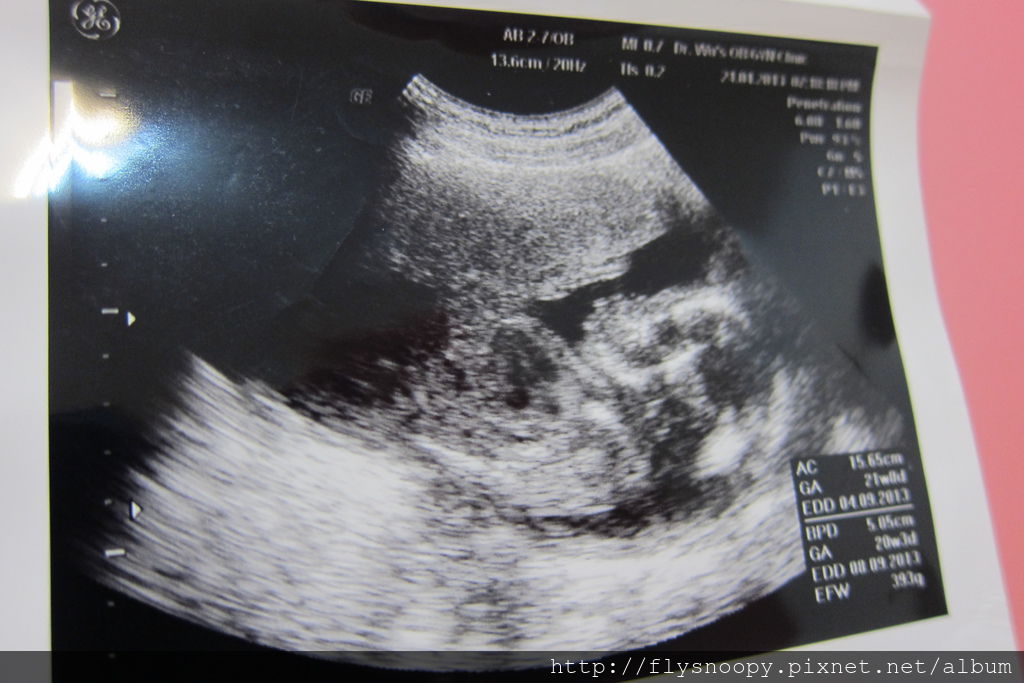

上面是4/28照的,可以清楚看見她的眼睛

果然baby一天一天長大囉~~~~